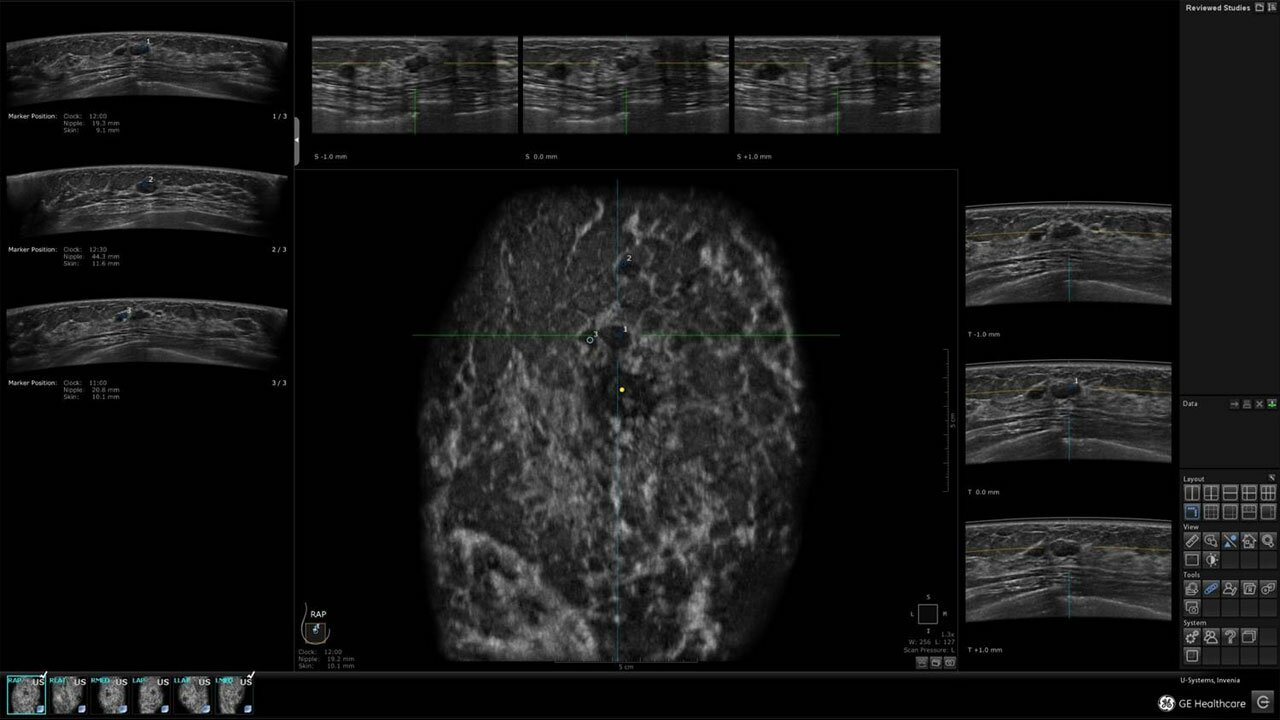

Клинические изображения

• Invenia ABUS Review Software - программное обеспечение для рабочей станци, устанавливается на рабочую станцию пользователя

• Отображение объемных 3D ультразвуковых изображений, которые состоят из традиционных поперечных и воссозданных коронарных и сагиттальных проекций

• Несколько протоколов для просмотра, которые могут быть настроены пользователем

• Многооконный просмотр: 4 - 12 изображений.

• Стандартизованная ориентация изображения:

• "толстый срез" в коронарной плоскости;

• поперечная;

• сагиттальная плоскость;

• радиальный и антирадиальный поворот изображения;

• Изменяемая толщина среза: 0,5 - 10,0 мм (шаг 0,5 мм)

• 360 ° APC - отображение области по "любой точке компаса"

• Одновременный просмотр двух изображений для сопоставления в коронарной плоскости